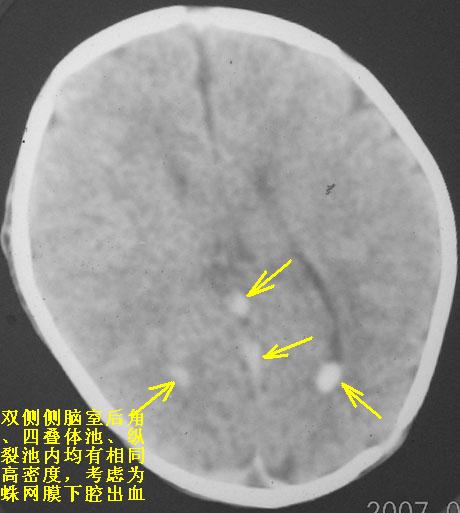

以下是引用rjg199343在2007-1-24 23:08:00的发言:[br]纵裂池、小脑幕、双侧脑室内高密度影,符合脑室、蛛网膜下腔出血。